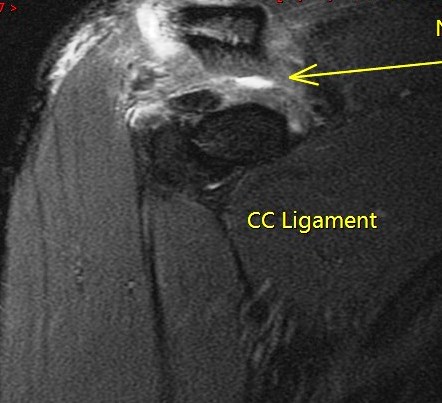

Figure 2 for case Grade 3 AC separation ( RID1895 )

Figure 2

The CC ligament is torn and the distal clavicle is elevated. Reference article.

Grade 3 AC separation ( RID1895 )